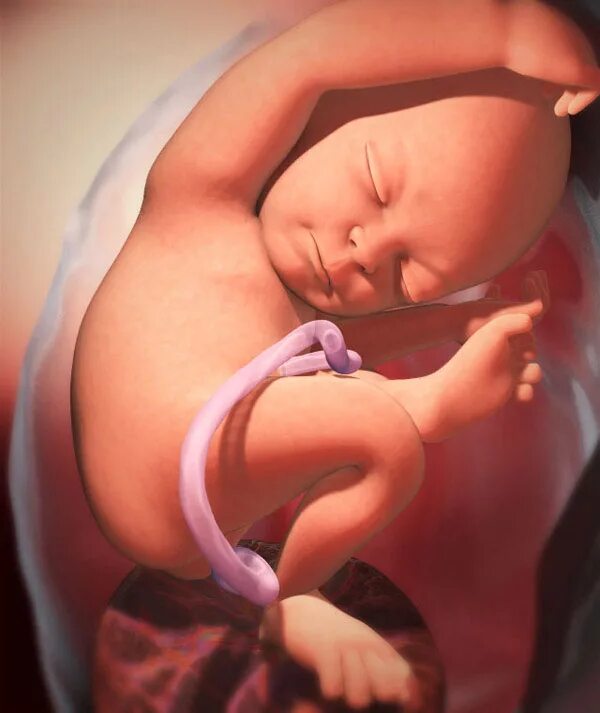

Как выглядит ребенок в 34 недели